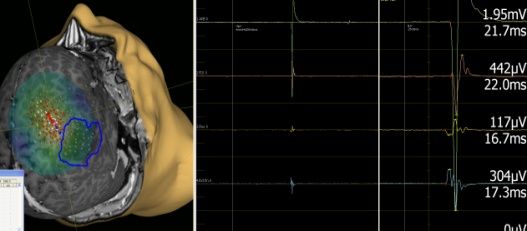

Akustisch evozierte Potentiale sind eine heterogene Gruppe von Potentialen, die sich bei Beschallung eines oder beider Ohren, in der Nähe des äußeren Gehörganges, gemessen gegen eine Referenz in der Scheitelregion, ableiten lassen. Diagnostisch am wichtigsten sind die Wellen I-V der frühen akustisch evozierten Potentiale. AEP spielen bei der Früherkennung von Prozessen am äußeren und inneren Ohr, am Hörnerv und bei Hirnstammerkrankungen eine wichtige Rolle.

AEP–Akustisch Evozierte Potentiale

Normalbefund vs Peaks schlecht reproduziert und verzögert

Da die frühen AEP, ebenso wie die SEP, stabil gegenüber pharmakologischen Einflüssen und unabhängig von der Bewusstseinslage sind, kommt auch ihnen eine wichtige Rolle bei der Beurteilung zur Prognose nach schweren Schädelhirntraumata und intrazerebralen  Blutungen auf Intensivstation zu.